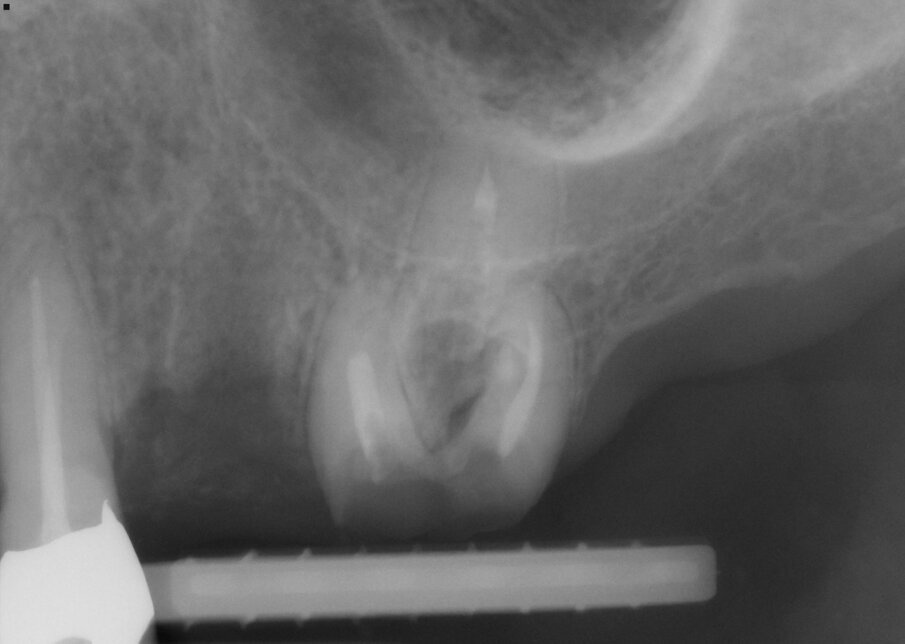

Fig. 1: Tooth #26 presented bent and diverging roots. The tooth was severely decayed.

The new, very thin Luxator P-series periotome made it possible to perform an atraumatic extraction with minimal loss of bone. Luxator P4, with its extremely sharp dual-edge blade, was used, followed by Luxator P1, once some space was created. Although the blades of these sophisticated instruments are reinforced with a titanium coating, they should only be used to cut the periodontal ligament and never to elevate the tooth. After sectioning the tooth and gently cutting the periodontal ligament, each root could easily be taken out with the help of diamond tweezers.